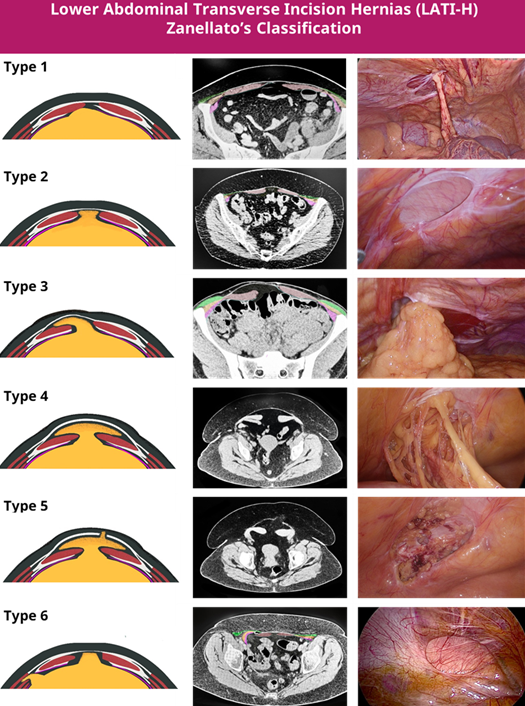

A new classification of these has recently been described by Zanellato et al. as shown below.

Lower abdominal transverse incisional / interparietal hernias (LATI-H) are a type of hernia where there is a defect in the posterior sheath, arising from a lower abdominal transverse incision, which subsequently causes hernias to form within the lower abdominal wall. The hernias in question do not necessarily breach the anterior fascia of the rectus sheath, making them difficult to detect clinically. Small defects in the abdominal wall are often asymptomatic and cause minimal discomfort, however, in other people they may cause debilitating symptoms.